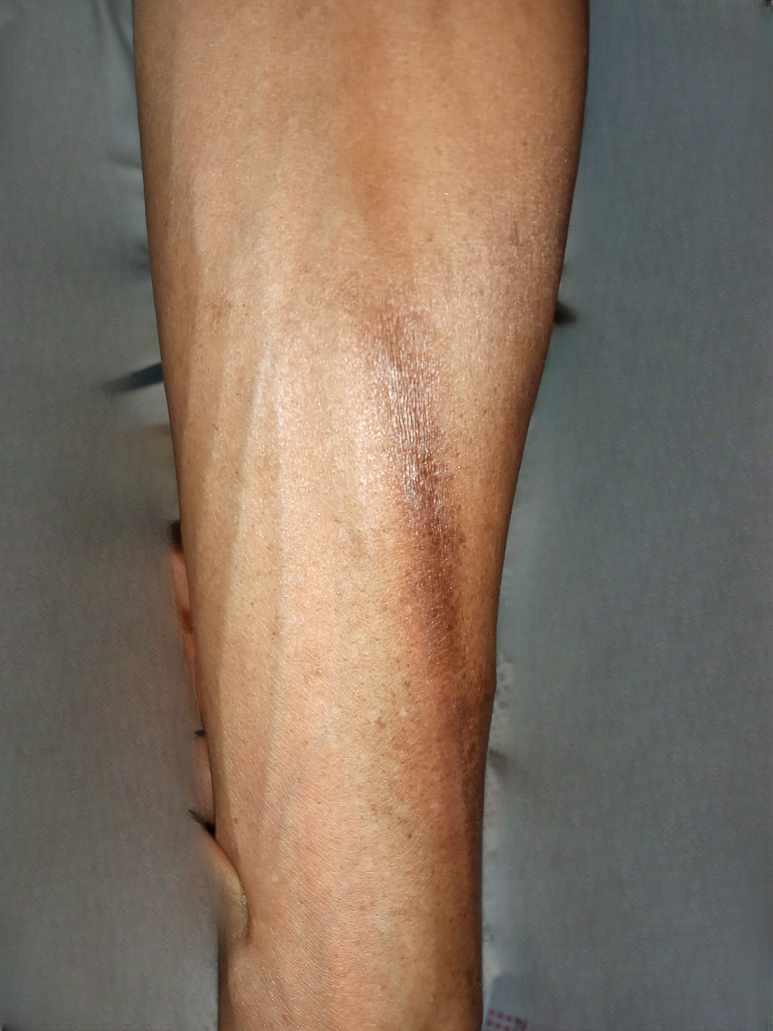

Results: Among 88 patients (84.1% female; mean age 45.8 ± 16.7 years), 31 (35.2%) developed at least one CRLC. Out of 193 chemotherapy cycles, 51 CRLC episodes (26.4%) were recorded, including phlebitis (15.0%) and extravasation (11.4%). Most frequent protocols were doxorubicin + cyclophosphamide (AC) and epirubicin + cyclophosphamide (EC), accounting for 33.0% of cases, followed by docetaxel monotherapy (25%). CRLCs occurred during the first four cycles (45.2%), predominantly grade 2 (82.4%), with favorable outcomes within 10 days (96.1%). Peripheral venous access was used almost exclusively (100% with CRLC vs. 96.5% without CRLC, p = 0.291). No statistically significant predictive factor was identified. In 9.1% of cases, delayed consultation caused extensive lesions requiring surgical excision, leading to a temporary chemotherapy interruption without permanent functional sequelae.

Conclusion: CRLCs are frequent in our resource-limited setting, affecting more than one-third of patients and one-quarter of chemotherapy cycles. Phlebitis and extravasation occurred mainly during the first cycles, with most events being moderate but some requiring surgical management. These findings highlight the urgent need to strengthen prevention strategies, staff training, and access to appropriate vascular devices in order to reduce their incidence and ensure treatment continuity.